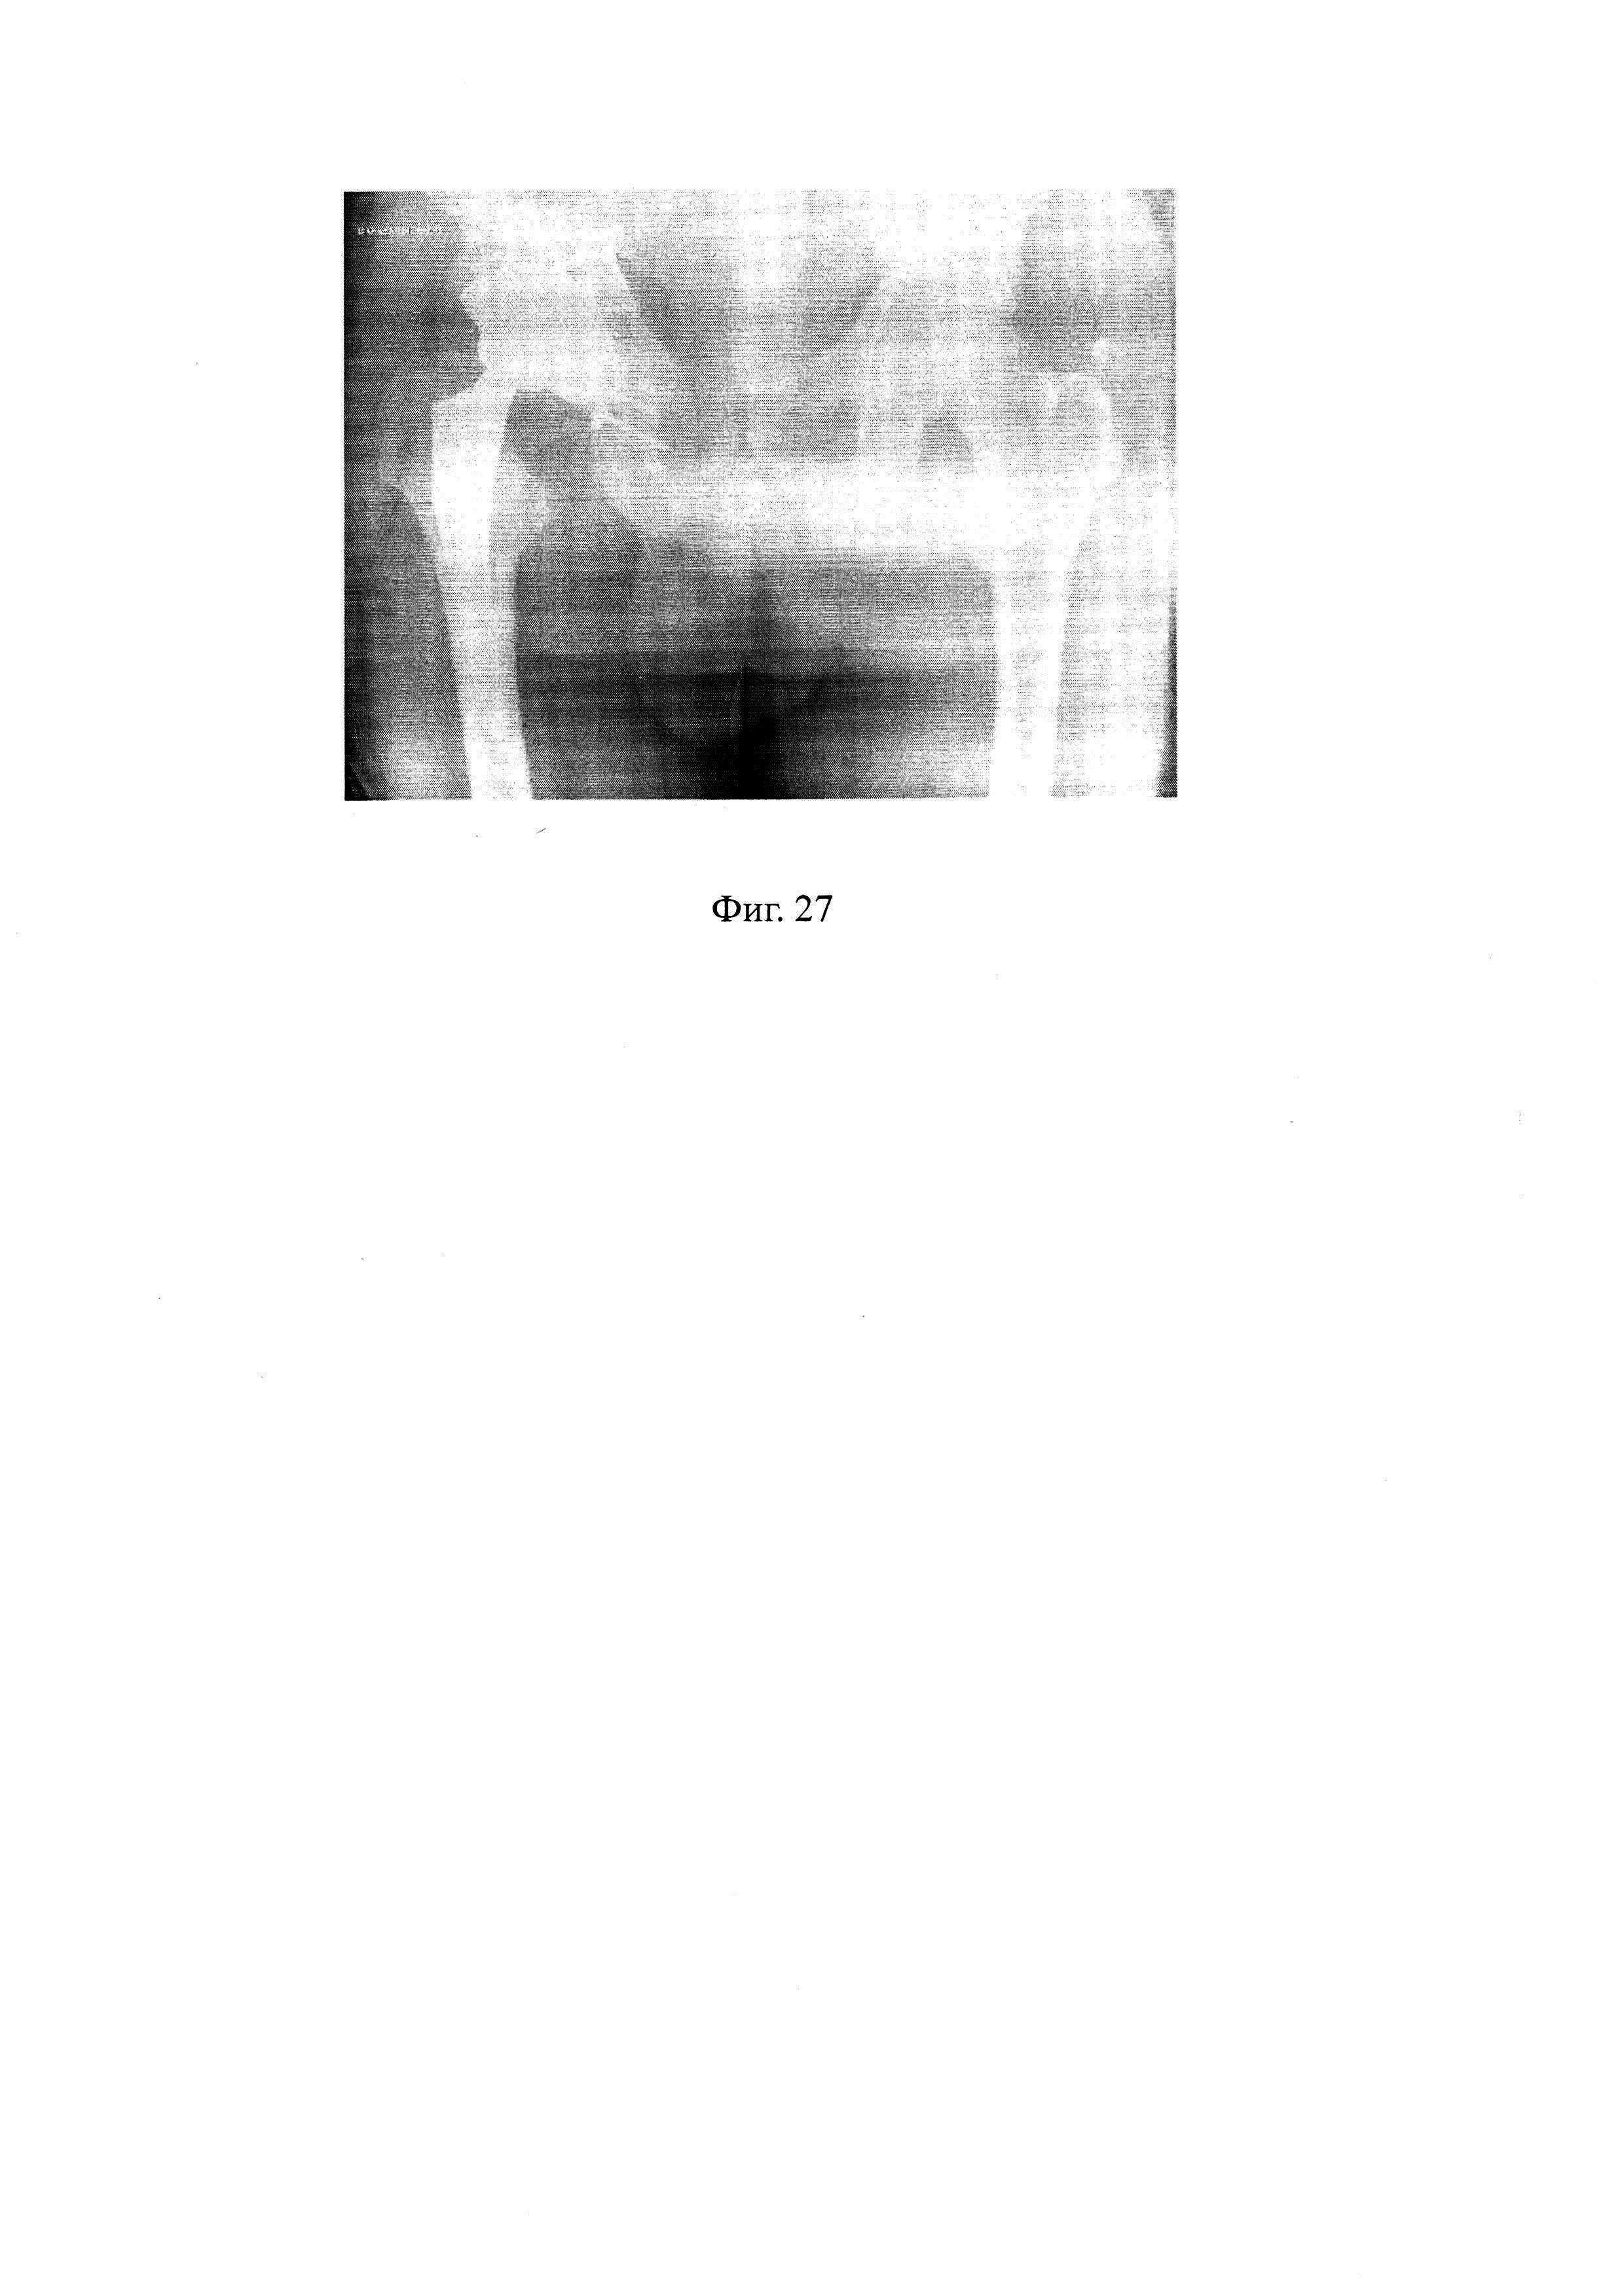

Изобретение поясняется следующими графическими материалами, где на фиг. 1 - 3D-модель, тестовая фигура, вид сбоку, фиг. 2 - 3D-модель, тестовая фигура, вид сверху, фиг. 3-3D-модель, тестовая фигура, вид снизу, фиг. 4 - 3D-модель, тестовая фигура, вид спереди, фиг. 5 - 3D изображение объемной модели таза в прямой проекции, фиг. 6 - 3D изображение объемной модели таза в прямой проекции, с фронтальной, сагиттальной и горизонтальной плоскостями, фиг. 7 - 3D изображение объемной модели таза в боковой проекции, с фронтальной, сагиттальной, горизонтальной плоскостями и плоскостью инклинации здоровой вертлужной впадины, фиг. 8 - 3D изображение объемной модели таза в боковой проекции, с фронтальной, сагиттальной, горизонтальной плоскостями, плоскостью инклинации и центром ротации здоровой вертлужной впадины, фиг. 9 - 3D изображение объемной модели таза в боковой проекции, с фронтальной, сагиттальной, горизонтальной плоскостями, плоскостью инклинации, центром ротации здоровой вертлужной впадины, с очерчиванием контуров здоровой вертлужной впадины и делением на три сектора, соответствующие лонной, седалищной и подвздошной костям, фиг. 10 - 3D изображение объемной модели таза в боковой проекции, с фронтальной, сагиттальной, горизонтальной плоскостями, плоскостью инклинации, центром ротации здоровой вертлужной впадины, подбор тестовых фигур для костей вертлужной впадины лонной, седалищной, подвздошной, фиг. 11 - 3D изображение объемной модели таза в прямой проекции, с фронтальной, сагиттальной, горизонтальной плоскостями, плоскостью инклинации, центром ротации поврежденной вертлужной впадины, фиг. 12 - 3D изображение объемной модели таза в прямой проекции, с фронтальной, сагиттальной, горизонтальной плоскостями, плоскостью инклинации, центром ротации поврежденной вертлужной впадины, очерчивание контуров лонной, седалищной, подвздошной кости образующих поврежденную вертлужную впадину, фиг. 13 - 3D изображение объемной модели таза в боковой проекции, с фронтальной, сагиттальной, горизонтальной плоскостями, плоскостью инклинации, центром ротации поврежденной вертлужной впадины, подбор тестовых фигур для костей поврежденной вертлужной впадины лонной, седалищной, подвздошной, фиг. 14 - 3D изображение объемной модели таза в боковой проекции, с фронтальной, сагиттальной, горизонтальной плоскостями, плоскостью инклинации, центром ротации поврежденной вертлужной впадины, с итоговой виртуальной реконструкцией, фиг. 15 - обзорная рентгенограмма тазобедренных суставов в прямой проекции при поступлении пациента, фиг. 16 - томограмма МСКТ тазобедренных суставов в боковой проекции при поступлении пациента, фиг. 17 - 3D изображение объемной модели таза в прямой проекции пациента, фиг. 18 - 3D изображение объемной модели таза в прямой проекции, с фронтальной, сагиттальной и горизонтальной плоскостями пациента, фиг. 19 - 3D изображение объемной модели таза в боковой проекции, с фронтальной, сагиттальной, горизонтальной плоскостями и плоскостью инклинации под углом 52° здоровой вертлужной впадины пациента, фиг. 20 - 3D изображение объемной модели таза в боковой проекции, с фронтальной, сагиттальной, горизонтальной плоскостями, плоскостью инклинации под углом 52° и центром ротации здоровой вертлужной впадины пациента, фиг. 21 - 3D изображение объемной модели таза в боковой проекции, с фронтальной, сагиттальной, горизонтальной плоскостями, плоскостью инклинации под углом 52°, центром ротации здоровой вертлужной впадины, с очерчиванием контуров здоровой вертлужной впадины и делением на три сектора, соответствующие лонной, седалищной и подвздошной костям пациента, фиг. 22 - 3D изображение объемной модели таза в боковой проекции, с фронтальной, сагиттальной, горизонтальной плоскостями, плоскостью инклинации под углом 52°, центром ротации здоровой вертлужной впадины, подбор тестовых фигур для костей вертлужной впадины лонной, седалищной, подвздошной пациента, фиг. 23 - 3D изображение объемной модели таза в прямой проекции, с фронтальной, сагиттальной, горизонтальной плоскостями, плоскостью инклинации под углом 52°, центром ротации поврежденной вертлужной впадины пациента, фиг. 24 - 3D изображение объемной модели таза в прямой проекции, с фронтальной, сагиттальной, горизонтальной плоскостями, плоскостью инклинации под углом 52°, центром ротации поврежденной вертлужной впадины, очерчивание контуров лонной, седалищной, подвздошной кости образующих поврежденную вертлужную впадину пациента, фиг. 25 - 3D изображение объемной модели таза в боковой проекции, с фронтальной, сагиттальной, горизонтальной плоскостями, плоскостью инклинации под углом 52°, центром ротации поврежденной вертлужной впадины, подбор тестовых фигур для костей поврежденной вертлужной впадины лонной, седалищной, подвздошной пациента, фиг. 26 - 3D изображение объемной модели таза в боковой проекции, с фронтальной, сагиттальной, горизонтальной плоскостями, плоскостью инклинации под углом 52°, центром ротации поврежденной вертлужной впадины, с итоговой виртуальной реконструкцией остеопластикой и вертлужным компонентом для пациента, фиг. 27 - рентгенограмма тазобедренных суставов в прямой проекции после операции пациента.

В данном случае у пациента процент дефекта для лонного сектора оставил 51%, для седалищного сектора составил 85%, для подвздошного сектора составил 75%. На основании полученных данных выполняют виртуальную реконструкцию на 3D-модели поврежденной вертлужной впадины (фиг. 26). На основании полученных данных для данного пациента выбран индивидуальный ацетабулярный компонент с полиаксиальным проведением винтов, реконструкция задней колонны пластиной, костная пластика, установка ацетабулярного компонента будет произведена под углом 52° в соответствии с его плоскостью инклинации. Далее выполняют хирургическое лечение с учетом полученных данных. После операции выполняют контрольную рентгенограмму тазобедренных суставов в прямой проекции (фиг. 27), на которой видно, что показатели оперированного сустава соответствуют параметрам здорового контрлатерального сустава. Данный рентгенологический контроль позволяет говорить о том, что реконструкция поврежденной вертлужной впадины произведена верно. Осложнений в раннем и позднем послеоперационном периодах не выявлено. Жалоб пациент не предъявляет.Отмечает отсутствие болевого синдрома, увеличение объема движений в левом тазобедренном суставе, восстановление опороспособности левой нижней конечности. Пациент удовлетворен полученными результатами.